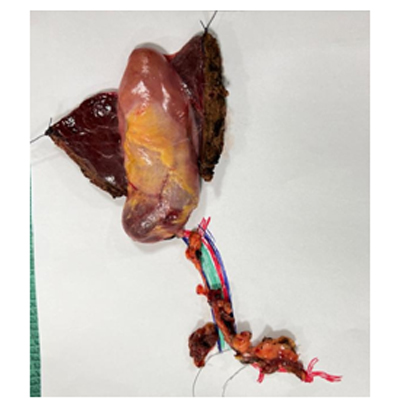

SURGERY FOR LIVER CANCER

LAPAROSCOPIC SURGERY FOR PANCREATIC TUMOUR

LAPAROSCOPIC WHIPPLES PROCEDURE